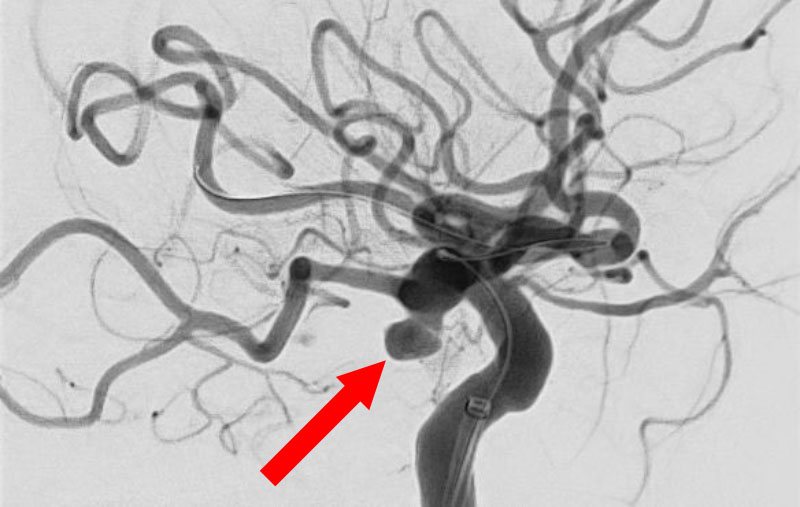

'26年4月

前交通動脈瘤

50代

大阪府の病院

No.1627 手術前